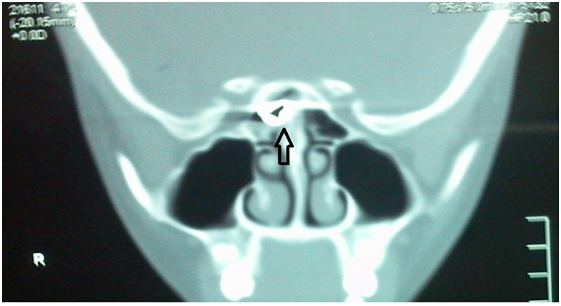

Anterior rhinoscopic examination was normal. Nasal endoscopic examination revealed nasal middle turbinate swelling in the region of the right middle meatus.1 The computerized tomography (CT) scan of the sphenoid sinus reveals a foreign body in the right side anterior to sella turcica as in Figure 1. Other section gives a shadow to posterior ethnocide sinus.

Figure 1 coronal CTscan showing air pellet in the sphenoid sinus.